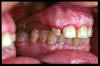

CM Edentulismo parcial, restos radiculares, caries y placa bacteriana